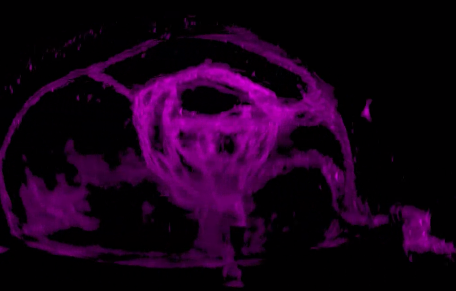

研究人員發(fā)現(xiàn),視網(wǎng)膜干細(xì)胞只能由視泡中間上皮細(xì)胞中一群雙潛能細(xì)胞產(chǎn)生,這群雙潛能細(xì)胞產(chǎn)生視網(wǎng)膜干細(xì)胞的同時(shí)產(chǎn)生視網(wǎng)膜色素細(xì)胞。為深入研究視網(wǎng)膜干細(xì)胞發(fā)育的分子機(jī)制提供了細(xì)胞譜系基礎(chǔ),為最終理解視網(wǎng)膜干細(xì)胞的產(chǎn)生和維持機(jī)制提供可能。

2017年7月26日,西雅圖華盛頓醫(yī)學(xué)院大學(xué)的科學(xué)家們?cè)凇禢ature》上發(fā)表名為“Stimulation of functional neuronal regeneration from Müller glia in adult mice”的論文,在小鼠的眼睛中再生了視網(wǎng)膜細(xì)胞。

雖然小鼠與人類(lèi)是不同的生物,但是,和人類(lèi)一樣,小鼠對(duì)于視網(wǎng)膜的損傷也是束手無(wú)策的。然而世間萬(wàn)物總是有一些特別的生物的存在,就像斑馬魚(yú),其視網(wǎng)膜中含有的Müllerglia細(xì)胞攜帶一種能讓它們?cè)偕幕颉狝scl1基因,在視網(wǎng)膜受損后,該基因會(huì)被激活進(jìn)行修復(fù)。

科學(xué)家們通過(guò)實(shí)驗(yàn),在成年小鼠眼中再生出了功能正常的視網(wǎng)膜細(xì)胞,這對(duì)于人類(lèi)視網(wǎng)膜細(xì)胞再生研究十分重要。研究人員表示,他們希望找到其他可以被激活的因子,以使Müllerglia細(xì)胞能再生出所有的視網(wǎng)膜細(xì)胞,這樣就有可能開(kāi)發(fā)出修復(fù)視網(wǎng)膜損傷的治療方法,讓那些因視網(wǎng)膜受損而失去視力的人重見(jiàn)光明。